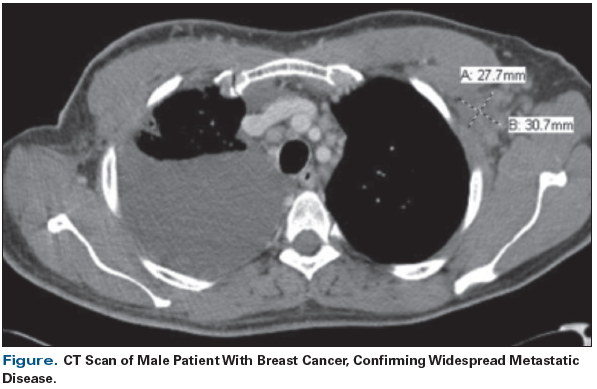

Figure. CT Scan of Male Patient With Breast Cancer, Confirming Widespread Metastatic Disease.

He underwent a course of chemoradiation for unknown primary in 2013, but in 2014 he developed new left supraclavicular and mediastinal adenopathy, and a right pleural effusion. He received a third round of chemotherapy with carboplatin and paclitaxel. Repeat imaging showed further progression of disease, with metastasis to various lymph nodes, right breast, right pleura, both lungs, and spleen. At this time, he sought care at our academic medical center. Cytology of his pleural effusion was positive for GATA3 and GCFDP-15, findings suggestive of breast cancer. Follow-up mammography showed increased density of the right breast, consistent with a primary breast lesion. Biopsy was performed and a genomic profile of the tumor was ordered. A PALB2 truncating mutation was reported.